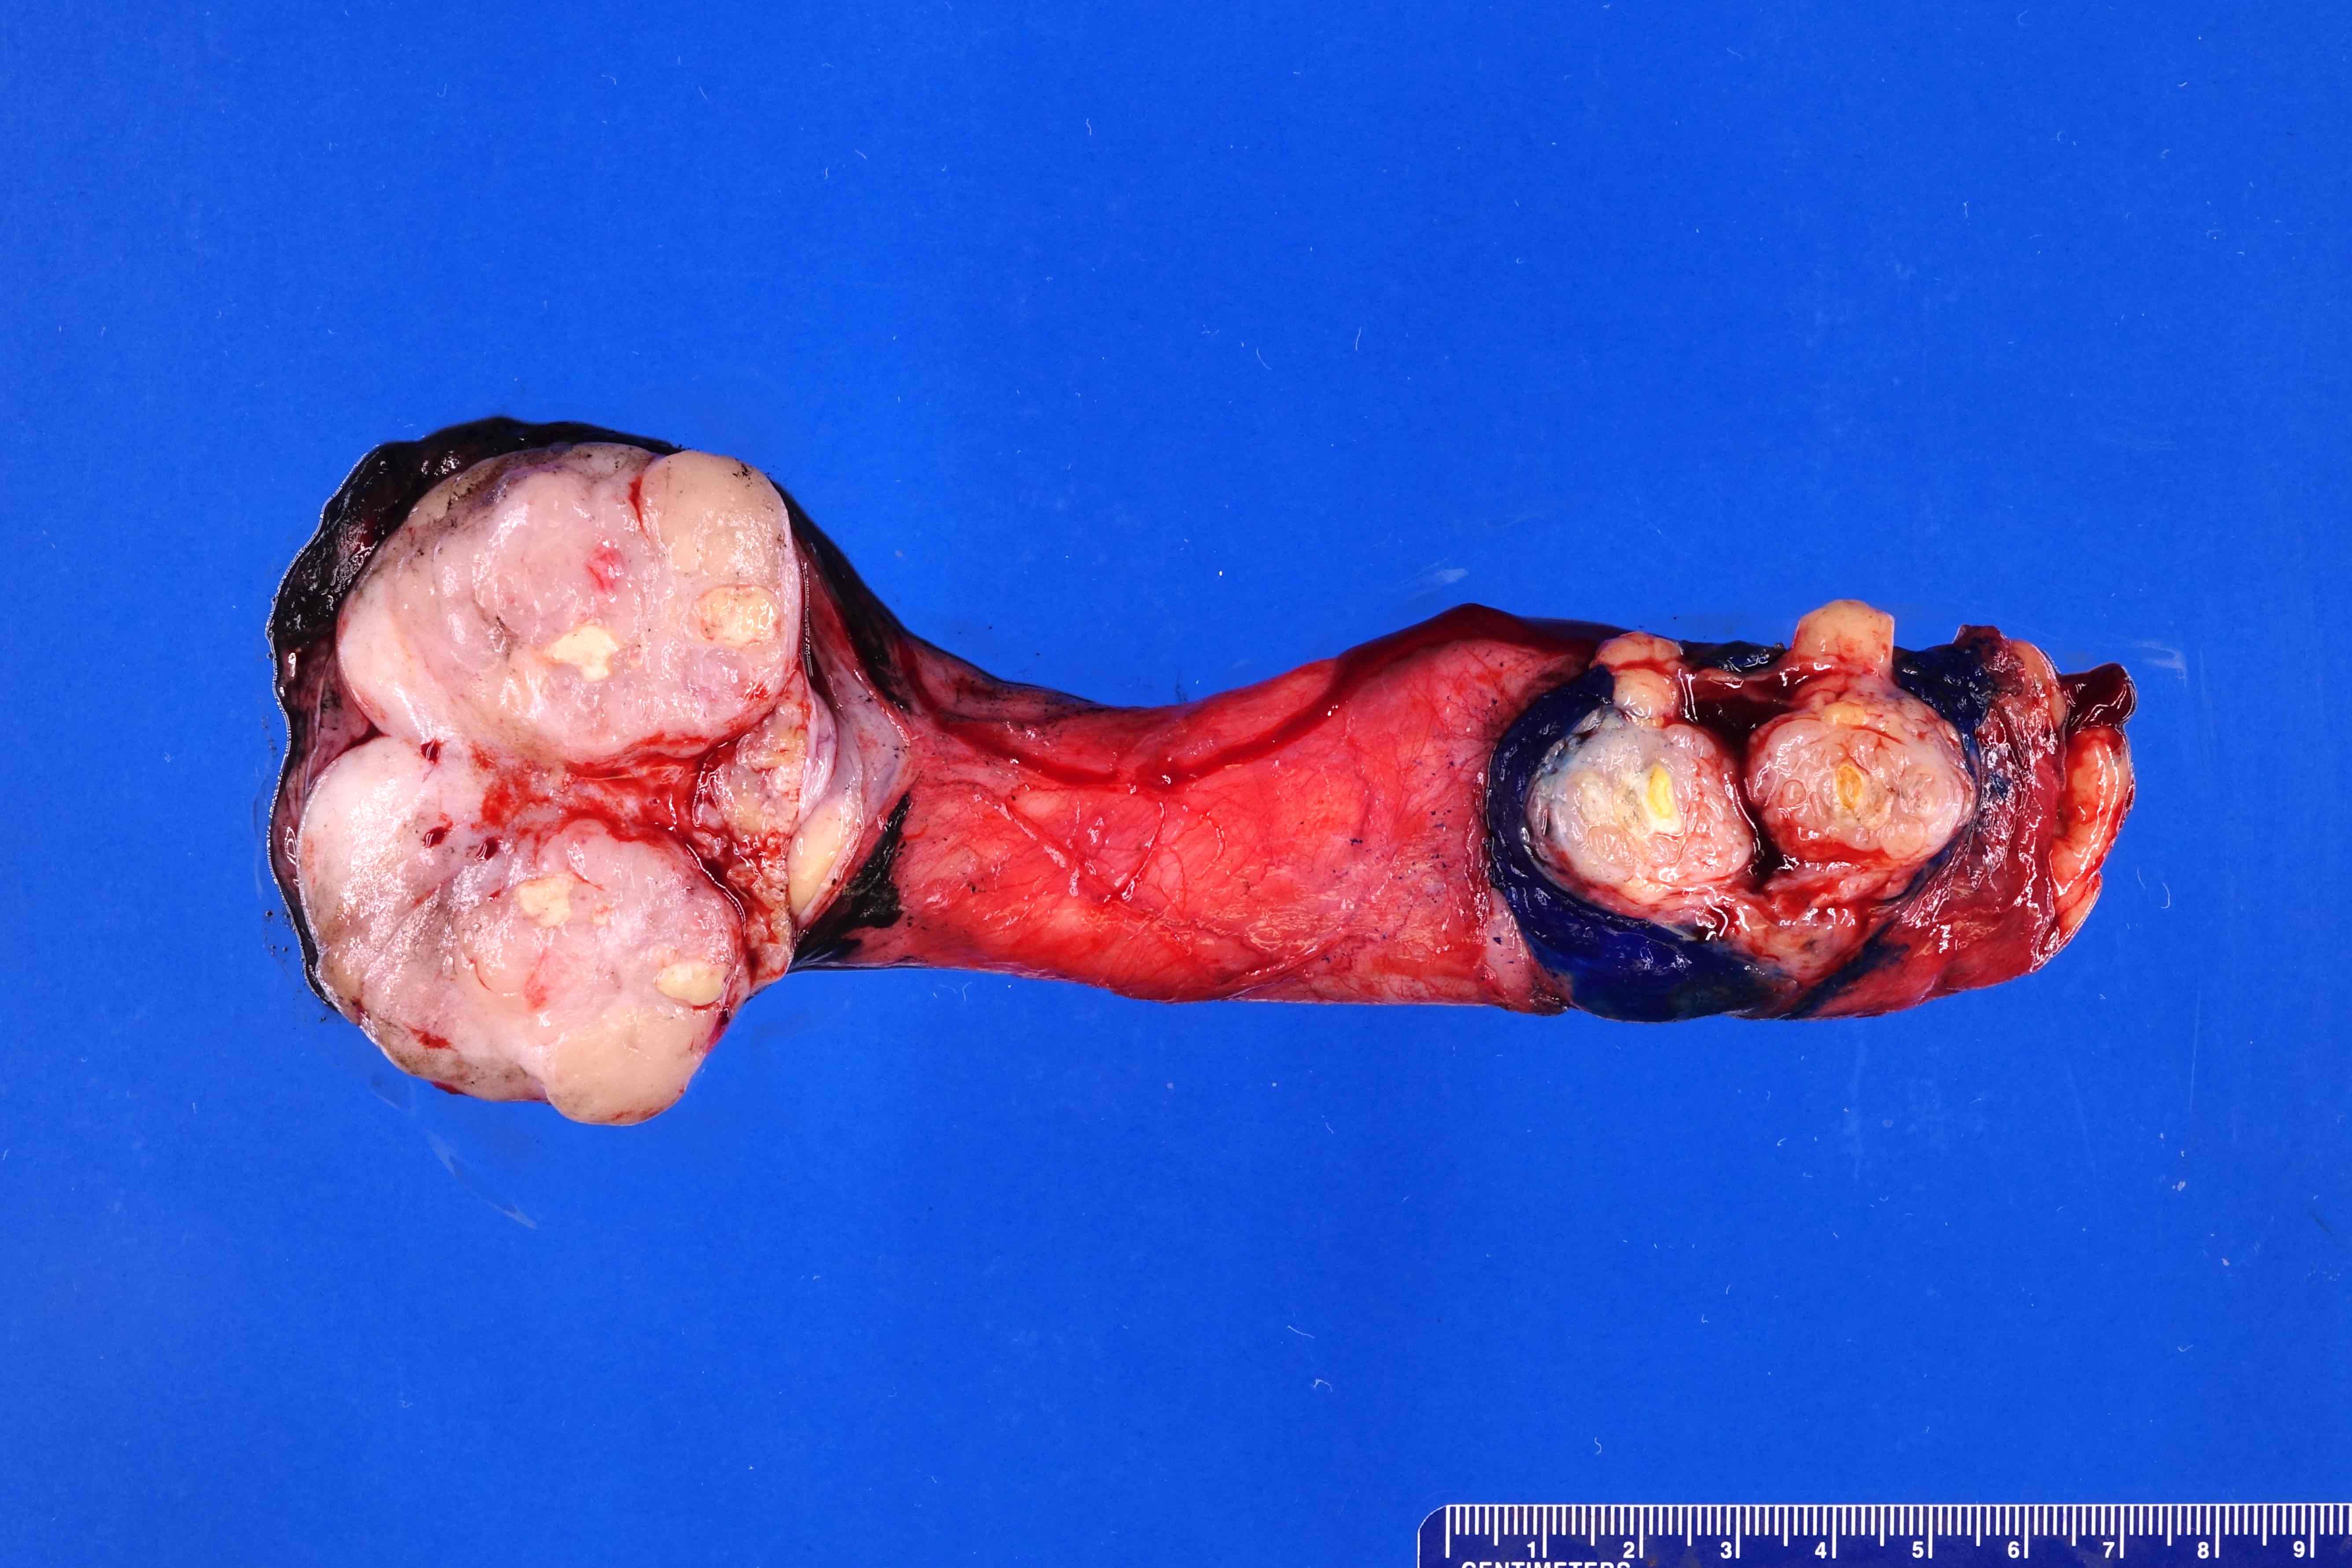

Gross images

Contributed by Debra L. Zynger, M.D.

Discontinuous spermatic cord (pM1)